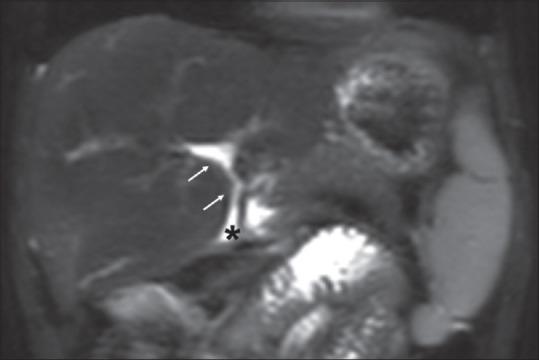

Twenty-one patients were included in the study. The male-to-female sex ratio was 1.6:1, the median age at surgery was 75 days (18-140 days), and the median age at magnetic resonance imaging (MRI) was 4 years (18 months-18 years). More than 2 years of follow-up was in seven patients. Left lobe hypertrophy was observed in six patients, right lobe hypertrophy was in three patients, intrahepatic biliary tract dilatation was in five patients, and altered signal intensity between intrahepatic ducts was seen in five patients. In addition, hypointense foci in the spleen were seen in one patient. Twelve children had normal weight for their age, ten children had the normal height for their age, and gamma-glutamyl transferase was elevated in all children. Only four children had a history of fever and jaundice.

本研究共纳入21例患者。男女比例为1.6:1,手术时的中位年龄为75天(18 - 140天),磁共振成像(MRI)时的中位年龄为4岁(18个月 - 18岁)。7例患者随访时间超过2年。6例患者观察到左叶肥大,3例患者观察到右叶肥大,5例患者观察到肝内胆管扩张,5例患者观察到肝内胆管之间信号强度改变。此外,1例患者脾脏出现低信号灶。12名儿童年龄别体重正常,10名儿童年龄别身高正常,所有儿童的γ-谷氨酰转移酶均升高。只有4名儿童有发热和黄疸病史。

结论

成功手术干预后存活的患者,其MRI/MRCP显示肝脏大体结构接近正常。偶尔可能出现扩张以及叶萎缩/肥大的表现,尤其是有胆管炎病史的患者。存活者的生长参数也在可接受范围内,肝功能正常。